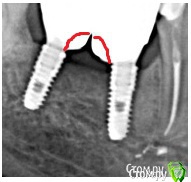

bullbull Опубликовано 27 августа, 2019 Поделиться Опубликовано 27 августа, 2019 2016 год 2019 Всё тот же осстем спустя 3 года. Может сделать времянки на полгода-год? Ссылка на комментарий

Nazim_NV86 Опубликовано 28 августа, 2019 Поделиться Опубликовано 28 августа, 2019 А для чего? Кость там, где ей и суждено быть. Вроде всё у вас неплохо там. Кортикалка сформирована. Ссылка на комментарий

Дмитрий М Опубликовано 29 августа, 2019 Поделиться Опубликовано 29 августа, 2019 2016.jpg2016 год 2019.jpg2019 Всё тот же осстем спустя 3 года. Может сделать времянки на полгода-год?кость уже не вернетсяпрофиль прорезывания Ссылка на комментарий